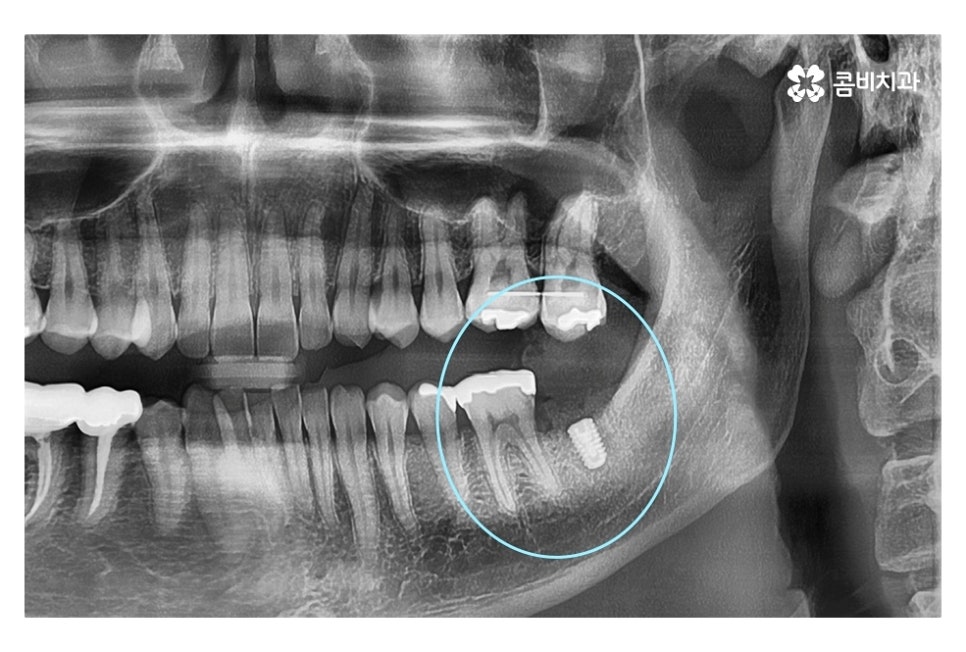

같은 환자분의 사진인데 좌측 치아의 경우 신경치료 후 크라운으로

마무리를 했지만 우측 어금니의 경우 치아의 대부분이

손상이 되어 결국 발치 후 임플란트를 하게 된 사례라고 할 수 있는데요.

신경치료는 자연치아를 살릴 수 있는 마지막 치료방법으로

신경치료를 진행할 수 없는 경우 발치 후 임플란트를 해야 하기 때문에